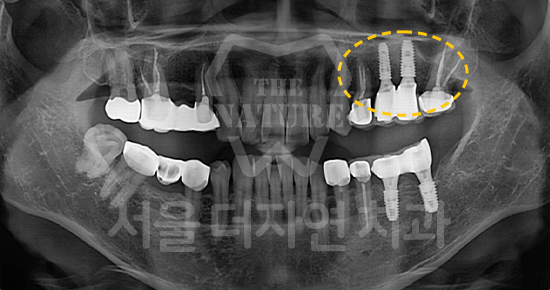

#Full Mouth Implants

-

BEFORE: 2022.12.15

AFTER: 2023.02.23